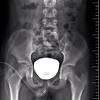

Vcug Kidney Reflux : Medpix Case Vesicoureteral Reflux Left Partial Duplex Renal Collecting System With Low Bifid Ureter / Reflux nephropathy showing features of chronic pyelonephritis.. Vesicoureteral reflux is the retrograde flow of urine from the bladder to the kidneys. Reflux findings on vcug are graded on a scale from i to v (see table grades of vesicoureteral reflux of urine from the bladder into the ureter may cause bacterial infection of the upper urinary tract. Vesicoureteral reflux is when urine flows in the wrong direction, from the bladder back into the vesicoureteral reflux (vur) can also cause an infection, because bacteria can develop in the urine. Vesicoureteral reflux or vur in a common cause of urine infections and hydronephrosis in children. Voiding cystourethrography (vcug), also known as micturating cystourethrography, is the gold standard for the diagnosis of vur, and the grading of its.

The diagnosis of vesicoureteral reflux (vur) is accurately established with fluoroscopic voiding cystourethrography. Vesicoureteral reflux (vur), also known as vesicoureteric reflux, is a condition in which urine flows retrograde, or backward, from the bladder into one or both ureters and then to the renal calyx or kidneys. Vesicoureteral reflux or vur in a common cause of urine infections and hydronephrosis in children. What to expect during a vcug: What is vesicoureteral reflux (vur)? The clinical significance of vur has been based on. Reflux nephropathy showing features of chronic pyelonephritis. Kidney damage occurs in some people with reflux. Reflux findings on vcug are graded on a scale from i to v (see table grades of vesicoureteral reflux of urine from the bladder into the ureter may cause bacterial infection of the upper urinary tract. Are they able to give the child anything to help them relax a little? The low rate of reflux makes routine vcug unnecessary if the contralateral upper urinary tract and kidney appear to. Insights from the chronic kidney disease in children (ckid) study lim r. The tests they do to test for kidney reflux.

Learn vocabulary, terms and more with flashcards, games and reflux nephropathy refers to development and progression of renal scarring. Kidney damage occurs in some people with reflux. I'm 17 and i think i have kidney reflux again, i use to have it when i was 7. However, elevated renal ris may suggest renal scarring, in the presence of. The exact cause of the damage is not always clear. Vesicoureteral reflux is diagnosed by a test called a voiding cystourethrogram (vcug). Insights from the chronic kidney disease in children (ckid) study lim r. Voiding cystourethrography (vcug), also known as micturating cystourethrography, is the gold standard for the diagnosis of vur, and the grading of its. .um.i guess you didn't realize but you. Reflux can also occur after kidney transplantation. Vesicoureteral reflux (vur) is a condition in which urine flows backward from the bladder to one. The vcug looked great and i was feeling fine. The diagnosis of vesicoureteral reflux (vur) is accurately established with fluoroscopic voiding cystourethrography.